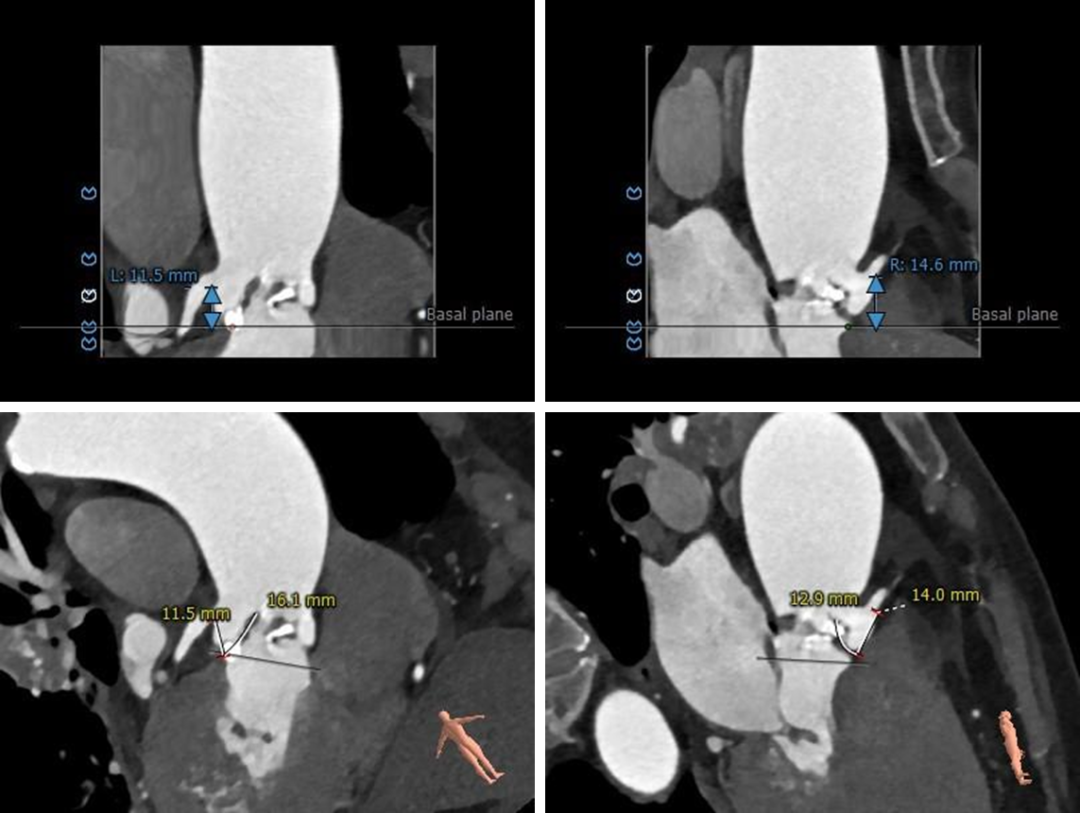

冠脉测量:

右冠开口高度可左冠开口偏低(11.5mm),左冠窦瓣叶冗长(16.1mm)。

● 右侧冠脉开口高度可,左侧冠脉开口较低(11.5mm),左冠窦瓣叶冗长(16.1mm),结合瓦氏窦宽度预估左冠阻挡风险极高。